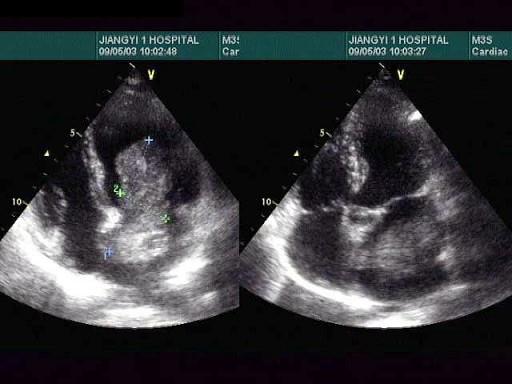

根据心尖四腔心切面声像图所示,超声诊断为?(?)A.左房血栓B.二尖瓣赘生物C.左房黏液瘤D.正常声像图E.以上都不是

问题 根据心尖四腔心切面声像图所示,超声诊断为?(?)

选项 A.左房血栓 B.二尖瓣赘生物 C.左房黏液瘤 D.正常声像图 E.以上都不是

答案 C